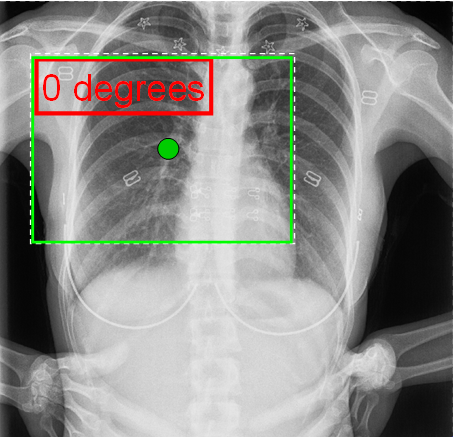

Equivalents to the above (moved slightly to separate centres of image and label) with NoRotate mode would now be:

With RotateAtLabelCentre

With RotateAtTextCentre

Similarly, the rotation point (the dot in the above) could be positioned elsewhere for RotateAtPoint mode.